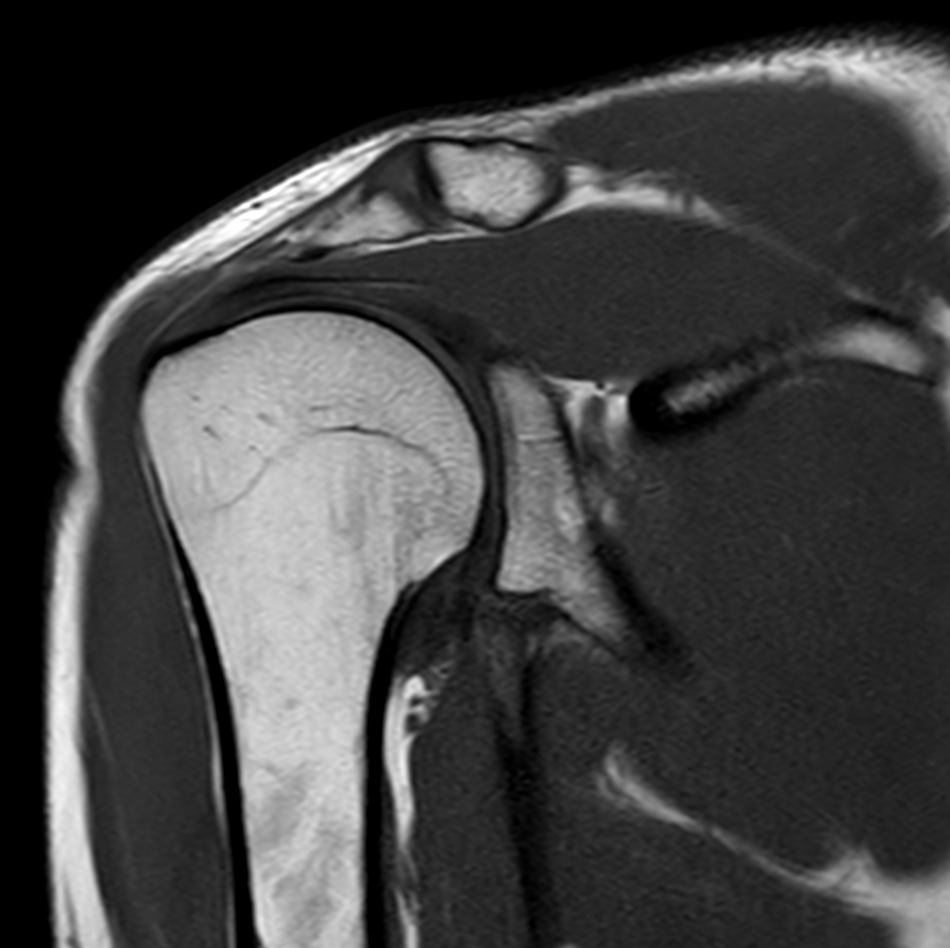

Coronal T2w TSE FatSat